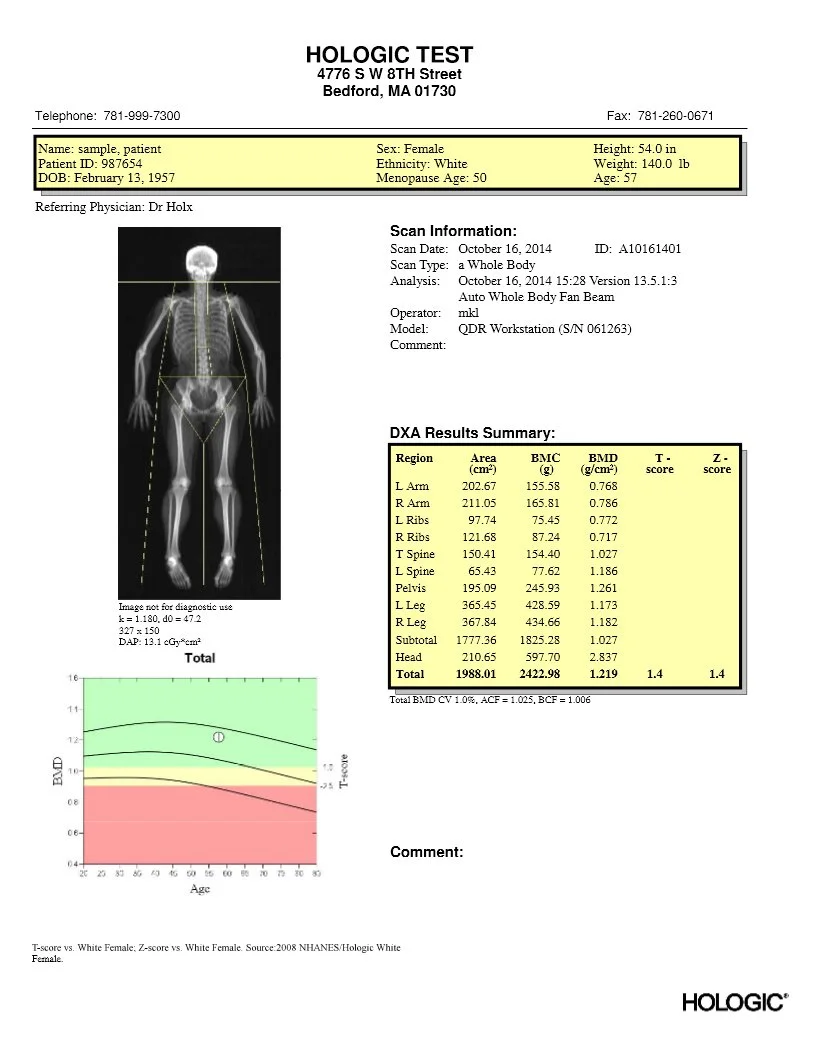

DEXA is the only widely used test that can accurately diagnose osteoporosis and osteopenia, and measure bone mineral density (BMD) over time.

For those concerned with bone health, specialized scans can be conducted that provide detailed analysis of key fracture-prone areas such as the spine and hip.